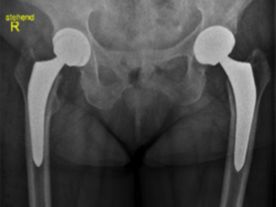

Sowohl beim Jugendlichen oder jungen Erwachsenen als auch beim älteren Menschen können Beschwerden im Hüftgelenk auftreten. Diese können sich langsam schleichend oder akut entwickeln. Da primär versucht wird, das eigene Gelenk solange wie möglich zu erhalten, ist eine genaue Abklärung essentiell, wenn Sie darüber nachdenken, das Hüftgelenk operieren zu lassen. Nach Ausschöpfen aller gelenkserhaltenden und konservativen Maßnahmen kann letztlich ein künstliches Gelenk für Sie der richtige Weg zurück zu einem schmerzfreien und aktiven Leben sein.

Als Ihr Spezialist für Hüftoperation und Teamleiter im Orthopädischen Spital Speising kann ich das für Sie am besten geeignete Operationsverfahren und die entsprechenden Implantate auswählen.

In jedem Fall verwende ich als Spezialist für die Hüftprothese nur die besten verfügbaren und international erprobten Implantate und Materialien, die für eine lange Lebensdauer Ihres neuen Gelenkes sorgen.